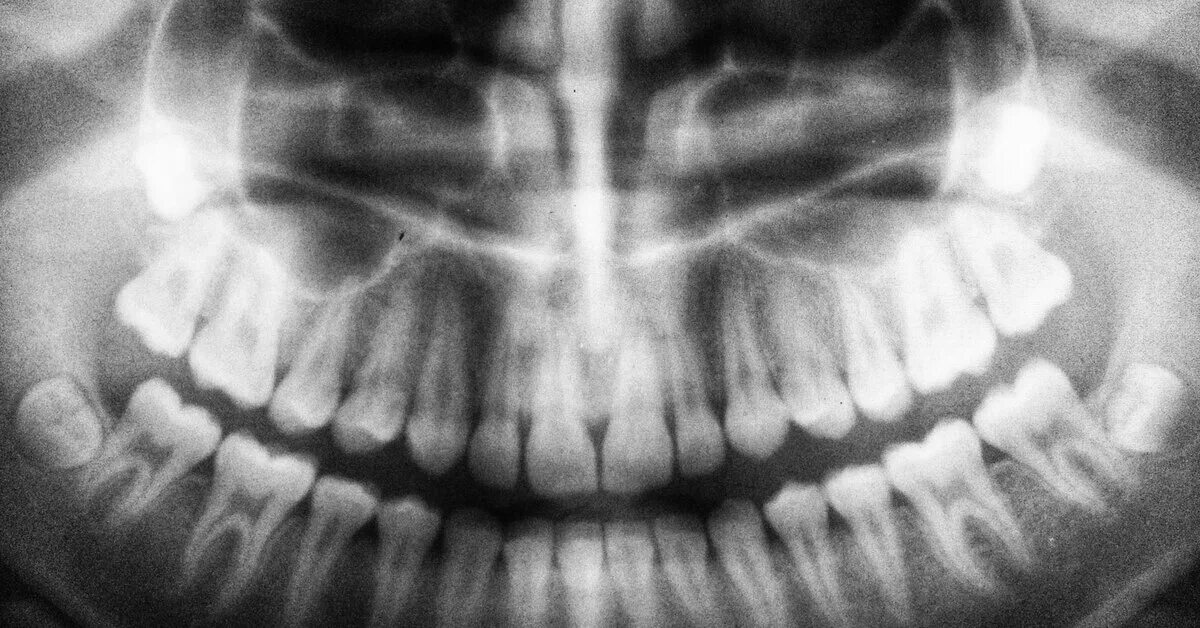

Снимок ротовой полости